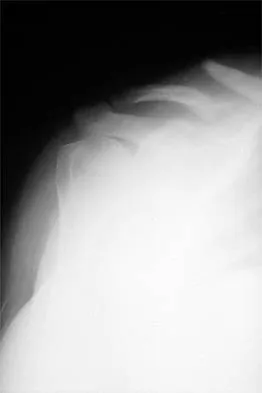

A 70-year-old man who underwent an uncomplicated large rotator cuff repair 6 months ago is now seeking a second opinion regarding persistent pain and weakness in his shoulder. Examination reveals that his incision is well healed and unreactive. The surgical report suggests that the tendons were secured back to bone with sutures through the greater tuberosity. Figure 28 shows a radiograph that was obtained 1 week ago. What is the most likely diagnosis?

Explanation

Symptoms can persist following a rotator cuff repair for a variety of reasons. In the early postoperative period, infection is the primary concern. Stiffness and loss of motion can occur because of postoperative scarring. Complex regional pain syndrome can occur but is rare, and the diagnosis is not made with a plain radiograph. This radiograph shows a superiorly migrated humeral head that articulates with the acromion, indicating that the repair has failed. While large to massive tears may fail more commonly than once thought, the clinical outcome may be satisfactory in many patients. Mansat P, Cofield RH, Kersten TE, Rowland CM: Complications of rotator cuff repair. Orthop Clin North Am 1997;28:205-213.